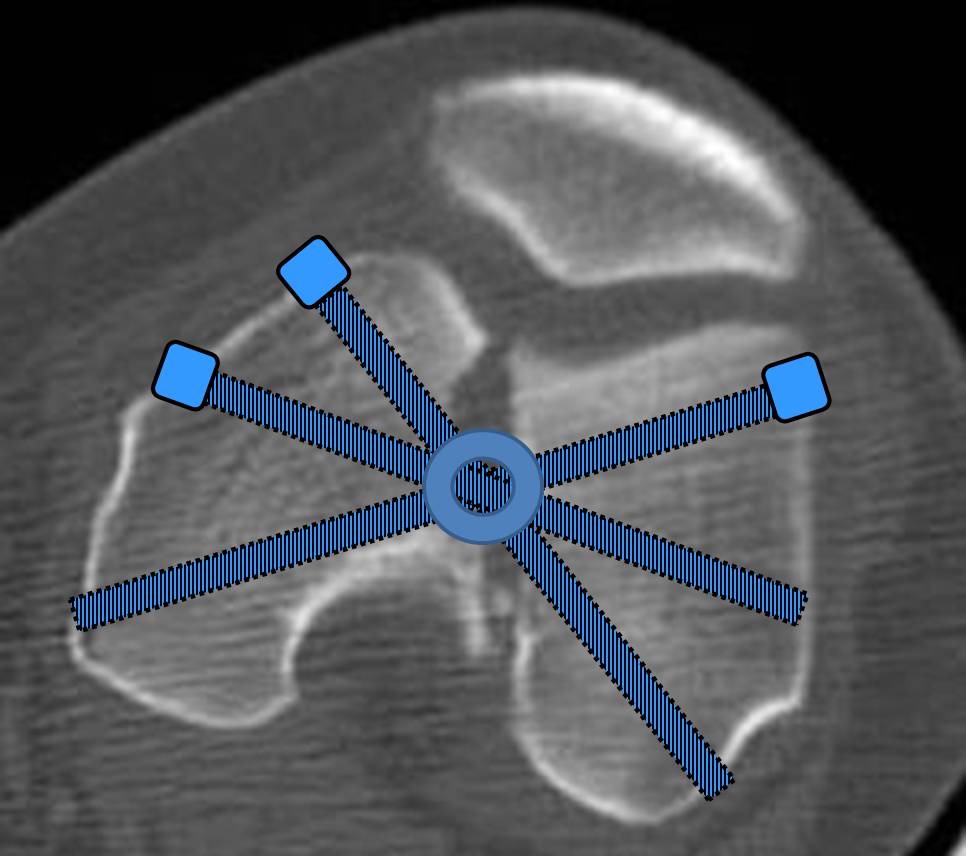

С моей точки зрения, безусловная ценность предложенного Вами, Александр Николаевич, стержня состоит в возможности введения блокирующих винтов максимально близко к суставной поверхности дистального отломка, что значительно расширяет показания для применения интерлокинга. Можно предположить, что в техническом плане таким образом ввести блокирующие винты является непростой задачей. Кроме того, все они расположены в одной плоскости на небольшом расстоянии друг от друга.

Мне представляется, что конструкция с максимальными прочностными характеристиками будет иметь вид предложенной во вложенном файле. Такую конфигурацию расположения блокирующих отверстий на дистальном конце имеет стержень для большеберцовой кости фирмы ChM. Для бедренной кости такой стержень мне неизвестен. Поэтому в необходимых случаях (хорошо, что такие случаи встречаются не часто), как вариант, мы используем custom made стержень.

Наш гвоздик, выпускаемый предприятием ЦИТО, тоже скорее из универсальных, хотя и с расширенными возможностями для дистальных переломов. Это овальное отверстие внизу задумывалось как динамическое для высоких переломов, очень дистально его разместили, чтобы не опасаться перелома гвоздя по этому отверстию. А возможность вот такого введения винтов, образующих "сборный клинок", обнаружилась года через 3 его применения.